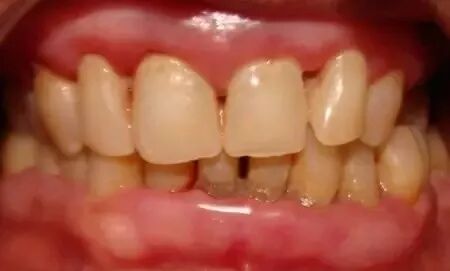

2、牙周疾病。长期口呼吸常伴有前牙,尤其上前牙的菌斑堆积、牙龈发炎。口呼吸时会带走口腔诸多水分,干燥的口腔环境缺少了唾液的机械冲刷和杀菌作用,菌斑堆积,牙龈发炎。而且,鼻呼吸的人唾液呈碱性,而口呼吸的人唾液偏酸,酸性环境也不利于牙齿和牙龈健康。

口呼吸者牙龈红肿、光亮。